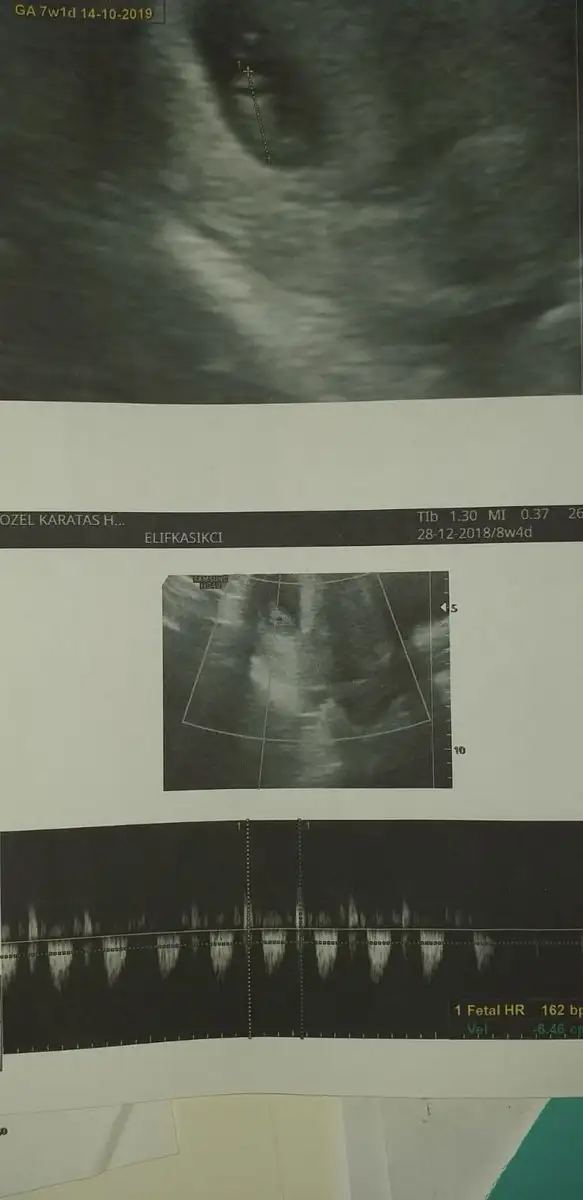

7 haftalik.Canım bebeğin düzgün fotosu yok mu burda çok ufak görünüyor

Canım bebeğin düzgün fotosu yok mu burda çok ufak görünüyor

7 haftalik.